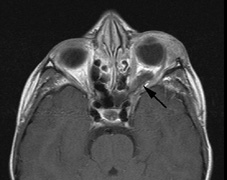

1. Schwannomas most commonly affect the fifth cranial nerve (CN), but any cranial nerve may be affected. In contrast to vestibular schwannomas (CN VIII), these typically do not grow large.84,90 Vestibular schwannomas (acoustic neuromas) are the classic finding in NF2 (Fig. 7). The risk for malignant transformation is low, but may be higher with radiation exposure.84,94

3. Other tumors: low-grade ependymomas and gliomas may affect the cervical spine and Brainstem (Fig. 7).84

Fig. 7. Neurofibromatosis type 2: Images of a 12-year-old boy with deafness and weakness in his arms and legs, whose father has bilateral deafness. Axial T2-weighted (a) and postcontrast axial (b) T2-weighted images reveal bilateral vestibular schwannomas, which are also known as acoustic neuromas (arrows). This is the classic finding of NF2. (b, c) Bilateral schwannomas are seen in Meckel's cave (arrowheads) and a (d) lower left cranial nerve schwannoma extends into the pars nervosa of the jugular foramen (arrow). (e) A part cystic and part solid enhancing ependymoma in seen within the cervical cord and medulla and within the distal cord and conus. (e, f) Thoracic schwannomas are present at numerous levels (arrowheads). Marked enhancement and thickening of the roots within the cauda equina also represent multiple schwannomas.